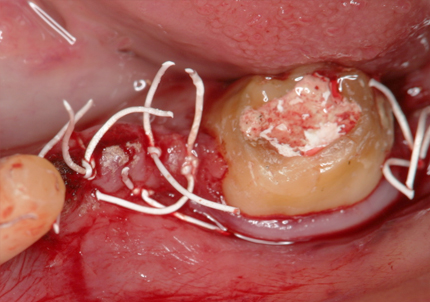

2.再生療法:エムドゲイン(2008年3月)

骨欠損部にエムドゲイン、バイオスを填入して、メンブレンにて閉鎖縫合する

➡バイオスとは

歯科で使われる骨補填材のひとつです。主に歯周病やインプラント治療で失われた骨を再生させる目的で使用されます。

➡メンブレンとは

歯科の骨再生治療で使われる薄い膜状の材料のことです。骨を再生させたい部分を保護し、治るためのスペースを確保する役割があります。